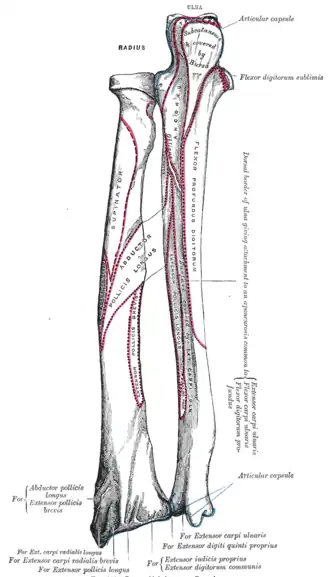

The dorsal border (margo dorsalis; posterior border) begins above at the back of the neck, and ends below at the posterior part of the base of the styloid process; it separates the posterior from the lateral surface. is indistinct above and below, but well-marked in the middle third of the bone.

The interosseous border (internal border; crista interossea; interosseous crest;) begins above, at the back part of the tuberosity, and its upper part is rounded and indistinct; it becomes sharp and prominent as it descends, and at its lower part divides into two ridges which are continued to the anterior and posterior margins of the ulnar notch. To the posterior of the two ridges the lower part of the interosseous membrane is attached, while the triangular surface between the ridges gives insertion to part of the pronator quadratus muscle. This crest separates the volar from the dorsal surface, and gives attachment to the interosseous membrane. The connection between the two bones is actually a joint referred to as a syndesmosis joint.

- Surfaces

The dorsal surface (facies dorsalis; posterior surface) is convex, and smooth in the upper third of its extent, and covered by the Supinator. Its middle third is broad, slightly concave, and gives origin to the Abductor pollicis longus above, and the extensor pollicis brevis muscle below. Its lower third is broad, convex, and covered by the tendons of the muscles which subsequently run in the grooves on the lower end of the bone.

The lateral surface (facies lateralis; external surface) is convex throughout its entire extent and is known as the convexity of the radius, curving outwards to be convex at the side. Its upper third gives insertion to the supinator muscle. About its center is a rough ridge, for the insertion of the pronator teres muscle.[3] Its lower part is narrow, and covered by the tendons of the abductor pollicis longus muscle and extensor pollicis brevis muscle.

Muscle attachments

The biceps muscle inserts on the radial tuberosity of the upper extremity of the bone. The upper third of the body of the bone attaches to the supinator, the flexor digitorum superficialis, and the flexor pollicis longus muscles. The middle third of the body attaches to the extensor ossis metacarpi pollicis, extensor primi internodii pollicis, and the pronator teres muscles. The lower quarter of the body attaches to the pronator quadratus muscle and the tendon of the supinator longus.

Posterior surface of radius (at left)

Posterior surface of radius (at left) -